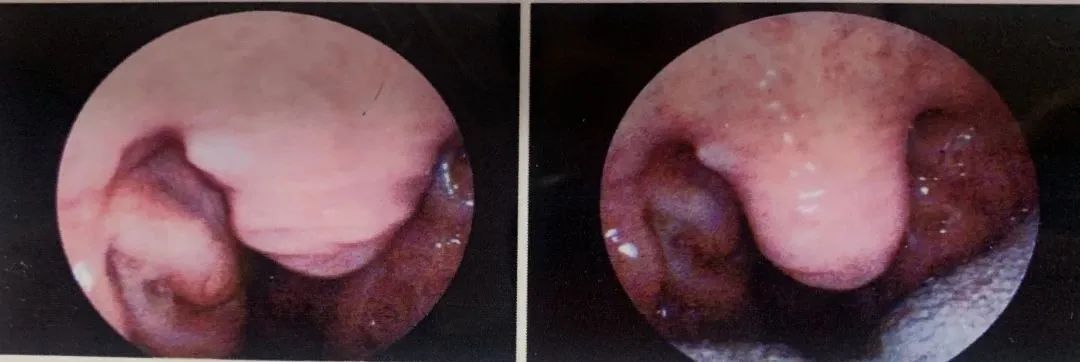

接診專家劉翠主任通過電子咽內鏡檢查查見:“咽部粘膜慢性充血,咽后壁淋巴濾泡增生,軟腭低垂,扁桃體Ⅱ度大,咽腔狹窄,咽側索肥厚。”

(咽內鏡檢查)